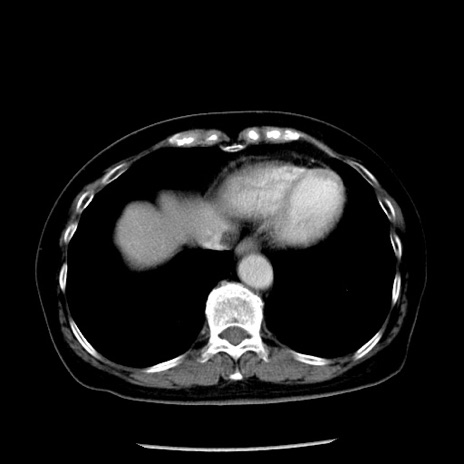

症例13(横断像)

【症例】70歳代女性

【主訴】腹痛、嘔吐

【現病歴】15時間程前(昨晩)より腹痛あり。今朝になっても症状の改善なく、嘔吐あり。腹痛も増悪あり、救急外来受診。

【既往歴】子宮癌全摘術後

【身体所見】意識清明、BP 121/72mmHg、P 74bpm、SpO2 100%(RA)、腹部:平坦・軟、腸雑音ほぼ聴取せず。下腹部・心窩部・臍左上に圧痛あり。反跳痛なし。

【データ】WBC 10600、CRP 0.15